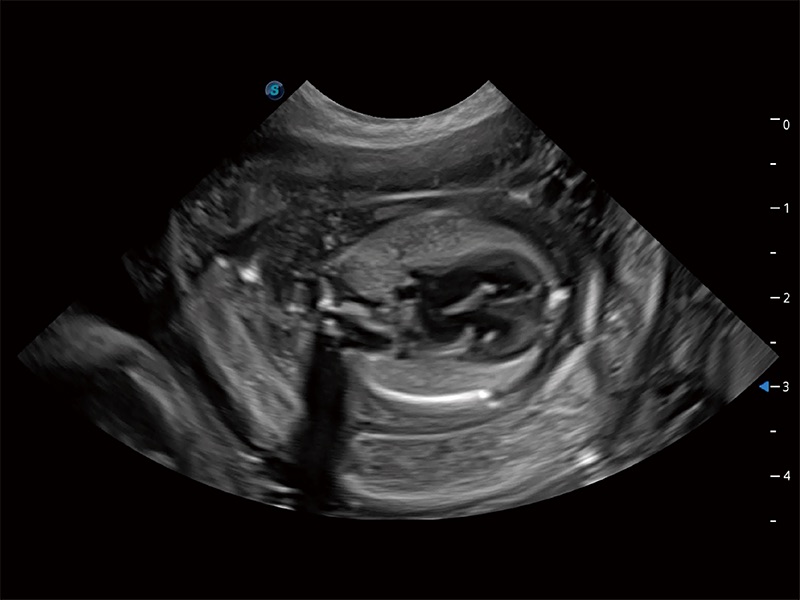

动物是人类最亲密的朋友和最值得信赖的伙伴。九州酷游也一直致力于探索动物专用的超声影像解决方案。全新推出的ProPet系列,是九州酷游在动物超声影像智能化、专业化、精准化的一次跨越式革新。动物不能用言语来表述自己的不适,通过超声影像,ProPet系列搭建了动物医生与不同物种沟通的“桥梁”,为动物医生注入了“治愈之力”。 ProPet 80 是九州酷游匠心打造的一款高端动物专用彩超,采用性能卓越的全新硬件架构,极大提升超声系统的运行效率和数据处理能力,帮助动物医生从容应对日益增多的挑战性病例和日益多样化的临床需求。

高性能和先进的临床应用工具可以为动物医生提供临床信心。ProPet 80 搭载了先进的腹部和浅表应用工具,帮助医生在日常临床实践中发挥前所未有的作用。